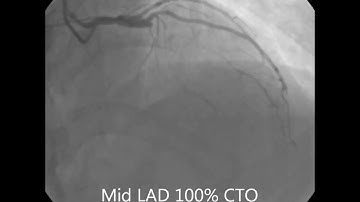

Complication of lad cto pci: cardiac tamponade